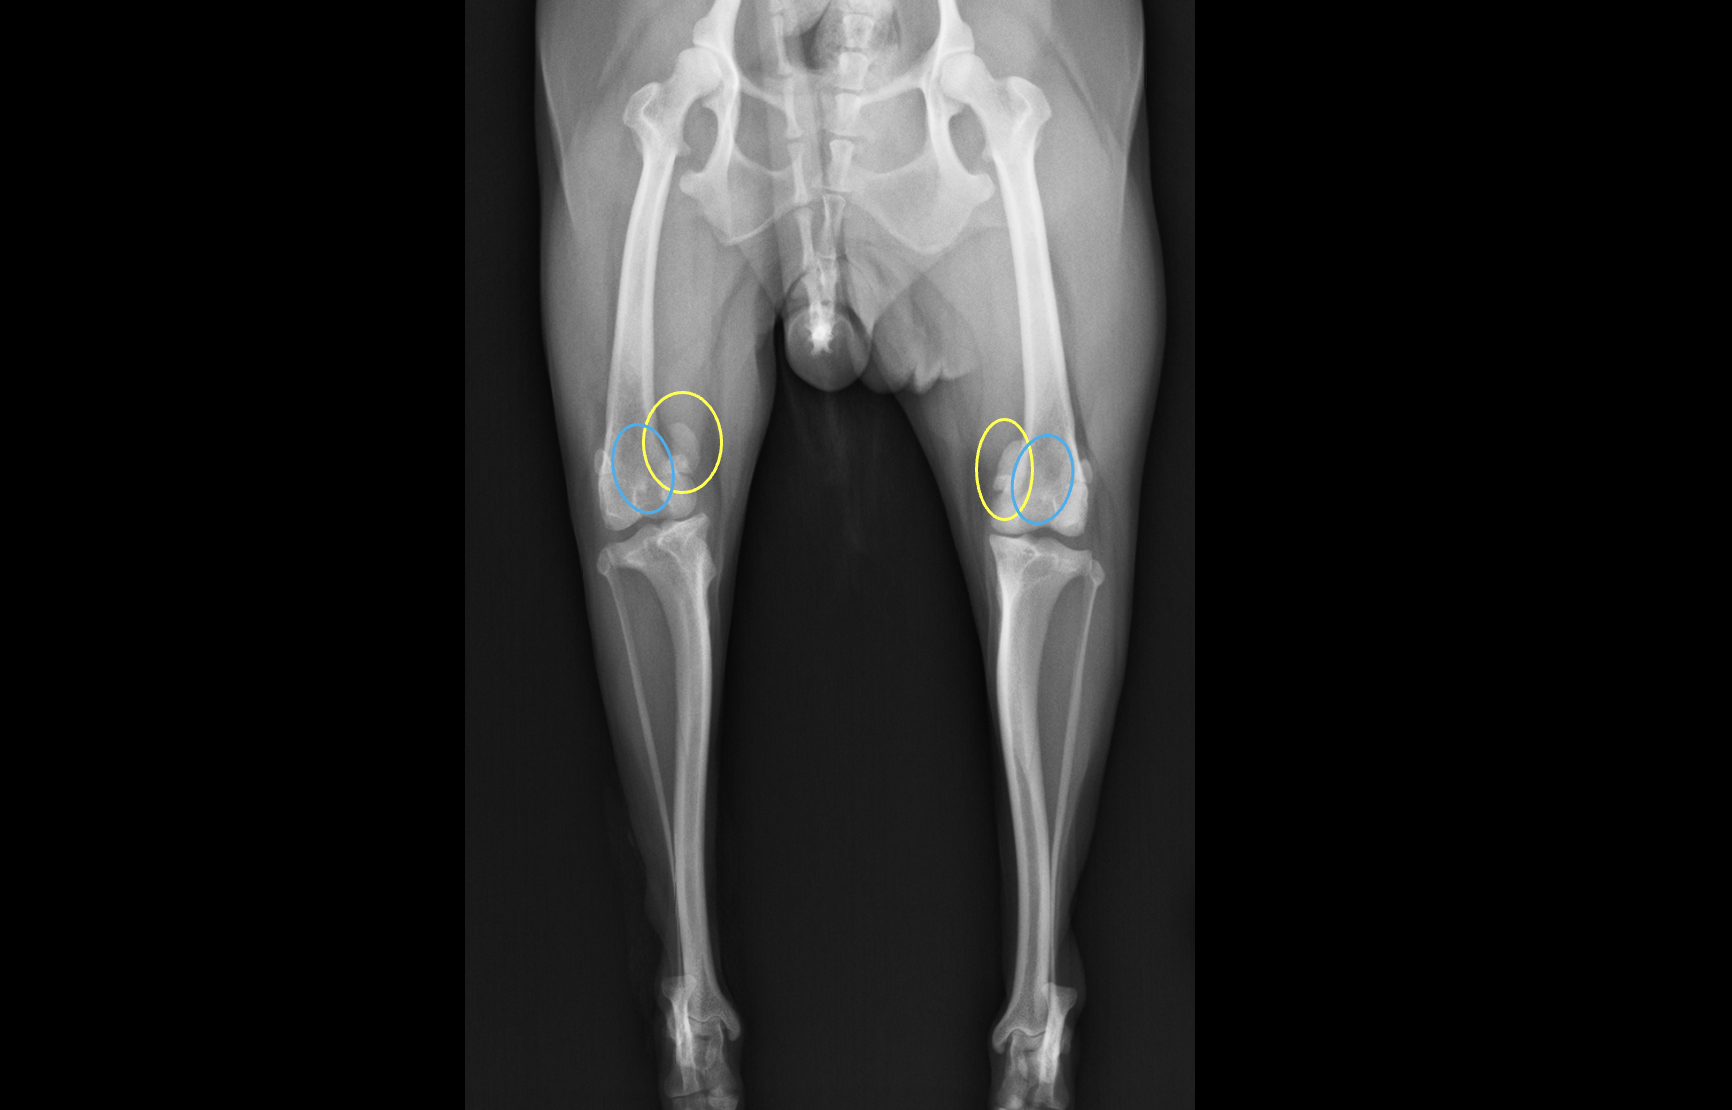

膝蓋骨内方脱臼(MPLといいます)は小型犬の後肢に影響を与える最も一般的な整形学的疾患の一つです。MPLの多くが小型犬であり、外傷なしで生まれつきもしくは生後早い段階で発生するため、遺伝的要因も関与している可能性が示唆されています。 MPLの要因は一つではなく、さまざまなことが複合的に合わさることで起きています。 1. コクサ・ヴァラ 大腿骨近位の内旋。 2. 大腿骨の遠位3分の1が内側に反っている。 3. 滑車溝の内側壁が浅いか欠損している。 4. 内側顆が低形成で、関節が傾いている。 5. 脛骨遠位端は外旋しているにも関わらず、脛骨粗面は内側への捻れている。 6. 脛骨近位部の内側への湾曲。 7.脛骨遠位端は外旋しているにもかかわらず、結果的に足先が内旋している。 このように骨の形態学的な異常から脱臼することがわかってきていますが、まだはっきりとしたことはわかっていません。

MPLではシングルトン分類というグレーディングシステムが一般的に利用されます。 Grade1:通常時には脱臼しないが、徒手によって脱臼がおきる。手を外すと正常位置に戻る。 Grade2:基本時にははまっているが、膝の屈伸や徒手により外れる。膝の屈伸や徒手で元に戻る。 Grade3:基本的に脱臼してしまっているが、徒手によって戻すことができる。手を離すと脱臼する。 Grade4:常に脱臼していて、徒手によっても戻すことができない 一般的にグレードが高いほど重症度が高いですが、必ずしも症状と一致しないのが難しいところです。 症状には時々跛行(ケンケンすること)する間欠的跛行と呼ばれるものから、完全に上げてしまって足をつくことができない(挙上といいます)状態などが挙げられます。お姉さん座りのように足を投げ出す、足を後ろに伸ばす仕草などが見られることもあります。 しかし、多くのMPL患者では症状がなく経過していきます。 膝蓋骨が脱臼することで膝の硝子軟骨というツルツルの軟骨が削れてしまい、その下の軟骨下骨が露出し、痛みになります。その後、その部分を自ら修復しようと繊維軟骨が覆っていきますが、その後関節炎が進行していきます。 そのような患者の中には中高齢になった段階で関節炎が起きて痛みが出るケースも見られます。また、そのほかにも膝の中の前十字靭帯が断裂して痛みが出て足をつくことができなくなったり、腰を痛めてしまったり、前肢を痛めてしまったりという患者が一定数います。